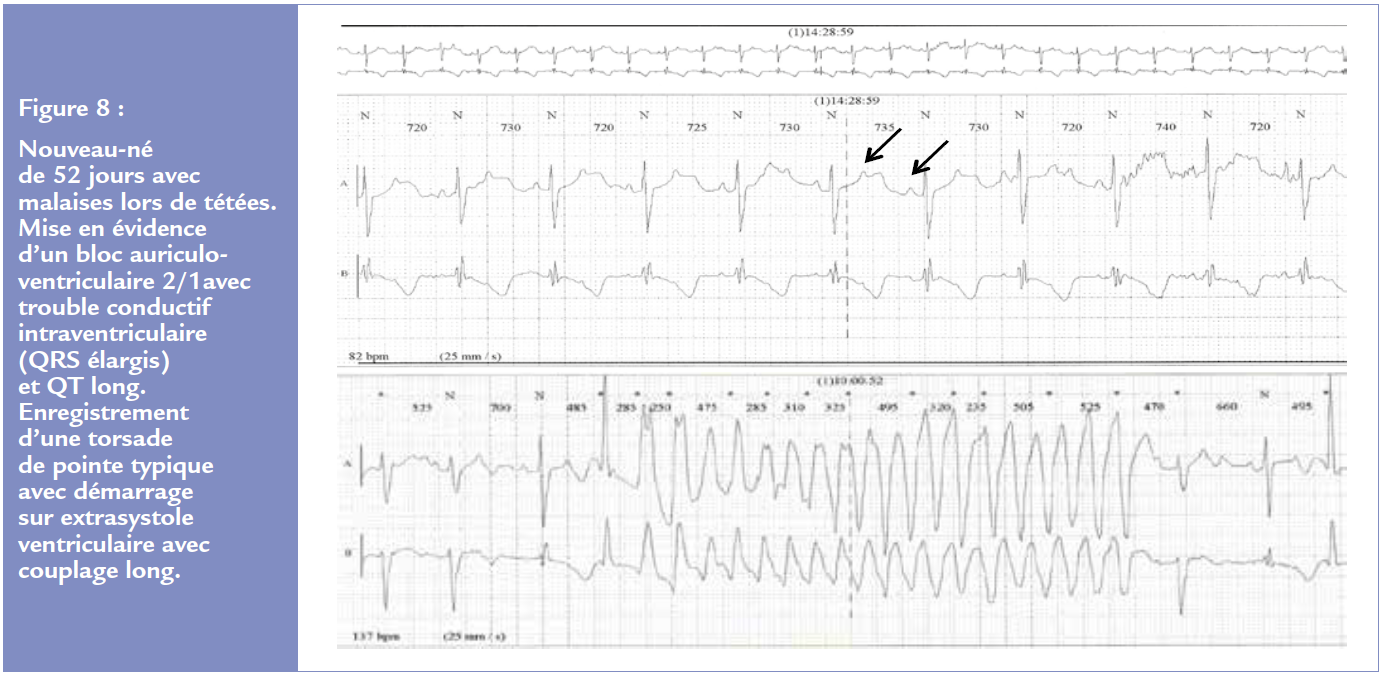

Les QT longs peuvent se révéler en période néonatale voire foetale par des torsades de pointe responsables d’absences/convulsions/syncopes/mort subite chez l’enfant. L’ECG intercritique sera très évocateur avec un intervalle QT allongé (plus de 490 ms chez le nouveau-né) ou un bloc 2/1 associé (en faveur d’un syndrome de QT long de type 2, Figure 8). Un typage génétique sera nécessaire associé à un traitement bétabloqueur par propranolol chez le nouveau-né en 3 prises puis par nadolol en 2 prises dès que possible. Une stimulation cardiaque définitive voire une sympathectomie thoracique pourra être proposée. Un défibrillateur pourra être discuté dans les cas les plus graves.